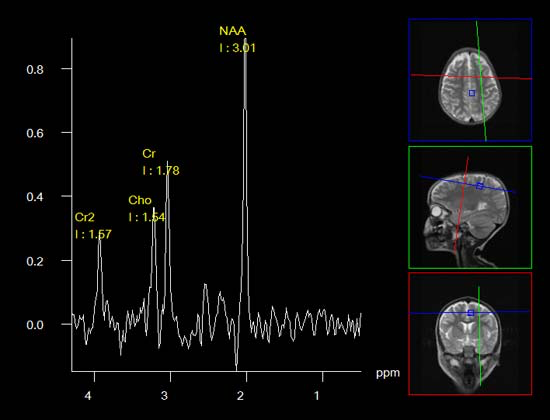

mrs.png